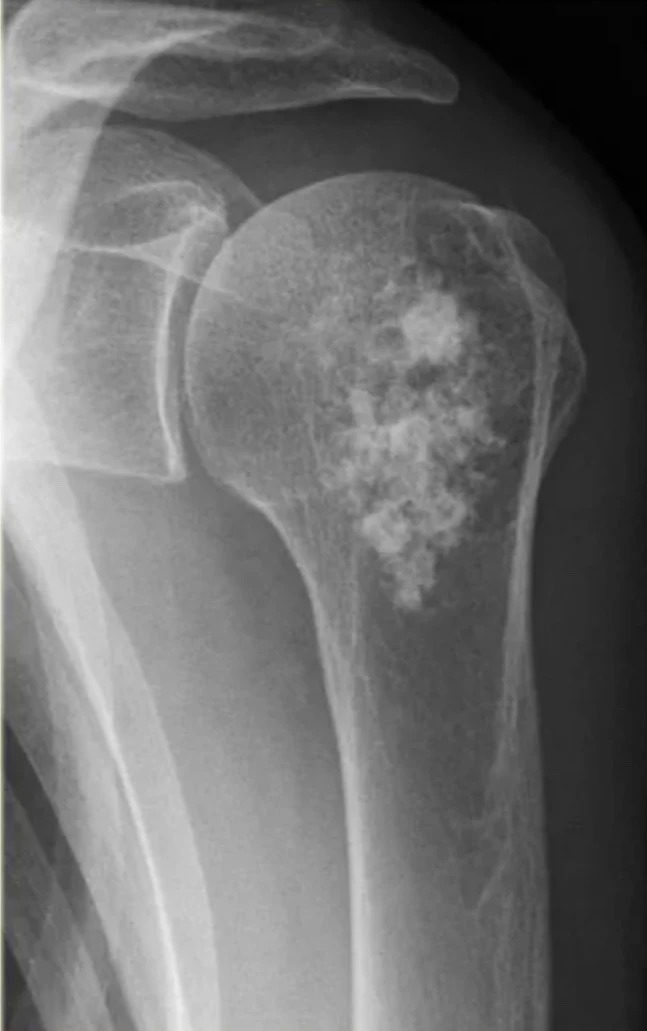

В основе инновационной разработки — радионуклид радий-223. Препарат «Ракурс, 223Ra» предназначен для лечения определённых видов онкологических заболеваний, преимущественно при метастазах в костях.

Радиоактивное излучение 223Ra целенаправленно воздействует на костные метастазы, уменьшая болевой синдром и улучшая качество жизни пациентов.